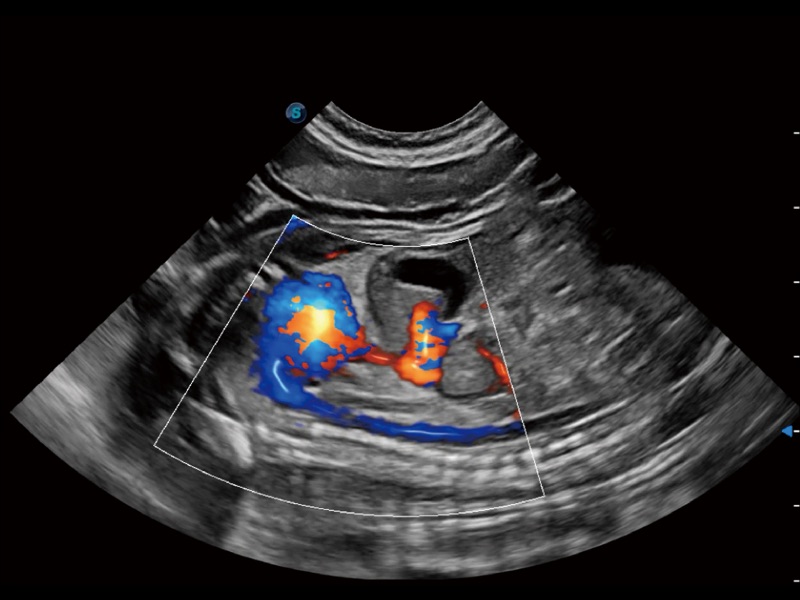

通过创新的 Matrix E自适应滤波器和超长时间域算法,极大提升超低速微细血流的检出能力,同时更精准地滤除软组织和噪声信号,为兽用医生提供以往无法通过常规血流获得的疾病诊断信息。

通过色彩血流和实时宽景相结合,可观察到完整的静脉或动脉的血流,方便医生检查。实时扫查过程中,如有任何操作失误也可以很容易地进行回扫擦除,而不会中断扫查。

通过360度任意调节3条M型取样线,在同一心动周期上观察心脏不同位置的运动曲线,得到准确的心功能测量数据,有效评估心肌运动及左心室功能。